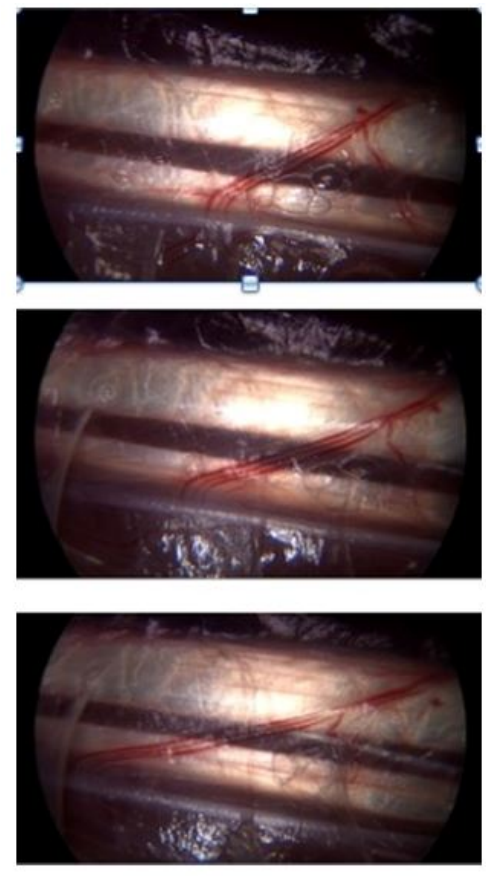

| Figure 3:The vessels of the peritendinous sliding network display different non-linear progression during movement within a homogeneous substance |

If we look for example, closely at the flexor tendons in the palm of the hand, we can observe two things; the wide variety of vessels around the tendons and the fact that, during movement of the tendon, there is no dynamic repercussion of the movement at the skin surface or in neighboring tissue, which remains stable.

If we analyse the images in figure 3 more closely, we observe that during flexion, the two large vessels diameter (150 microns) are indeed moving apart. However, compared to the smaller vessel, (30 microns) not only does the larger vessel move faster, but the two vesssels move at different speeds. We know this because the distance between them has doubled.

We can conclude two things.

- There is therefore obviously some kind of force absorption system.

- There are several forms of speed and progression.